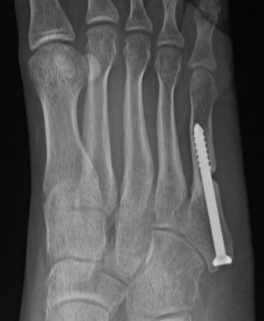

Intramedullary Screw

Screw fixation Zone 2 nonunion

Screw fixation Zone 3 nonunion

Technique

Entry point

- 5th metatarsal is not straight

- high and medial to get straight shot

- avoids plantar insertion peroneus brevis

- screw diameter 3.5 / 4.5 / 5.5 / 6.5

- screw threads must be distal to fracture site to allow compression